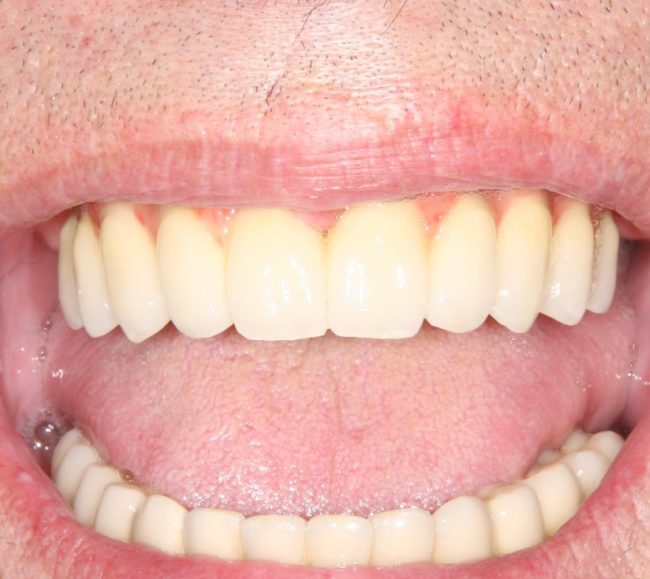

И вот, в жизни Марии наступил долгожданный день — окончательная фиксация керамических коронок на установленные имплантаты:

При этом, она ни дня не оставалась без зубов, была полностью социализирована и жила обычной жизнью. Спустя 5 месяцев после удаления, поставленную Марией клиническую задачу можно считать решёной. Но это с её точки зрения. С нашей же, всё самое интересное только начинается.

Вот клиническая картина и рентгенологический контроль через 2,5 года после имплантации и протезирования:

Как видите, под приемлемыми объёмами и состоянием десны в области имплантатов скрывается надёжный фундамент — восстановленная и сохраненная с помощью аугментации костная ткань, состояние которой за два с половиной года только улучшилось.

С точки зрения функционала, Мария не чувствует принципиальной разницы между естественными здоровыми зубами и коронками на имплантатах (последние она находит «более симпатичными») По её словам, она и думать забыла об имплантатах, а прошлые мучения с зубами кажутся ей «ночным кошмаром».